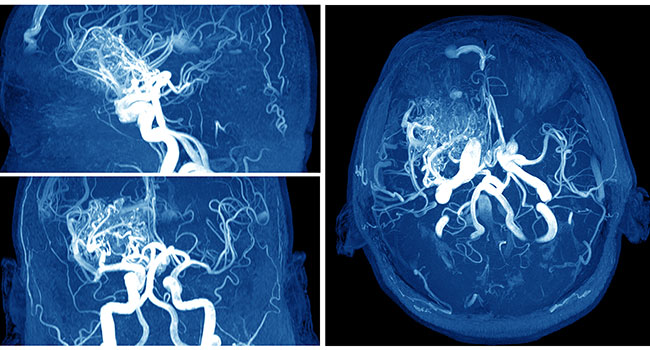

Una imagen de tomografía usa una serie de rayos-X para crear una imagen detallada del cerebro. En éstas se puede observar si hay hemorragia, tumor, infartos u otras alteraciones. Puede ser necesaria la utilización de medio de contraste para observar claramente los vasos sanguíneos del cuello y del cerebro con mayor precisión.

Le da al médico una imagen del estado de los vasos sanguíneos que alimentan al cerebro, así como detectar si existe un área con hemorragia.

En este estudio el médico inserta un catéter muy delgado en la ingle y lo lleva hasta la carótida y las arterias vertebrales, donde inyecta un medio de contraste para observar en detalle los vasos sanguíneos del cuello y cerebro.